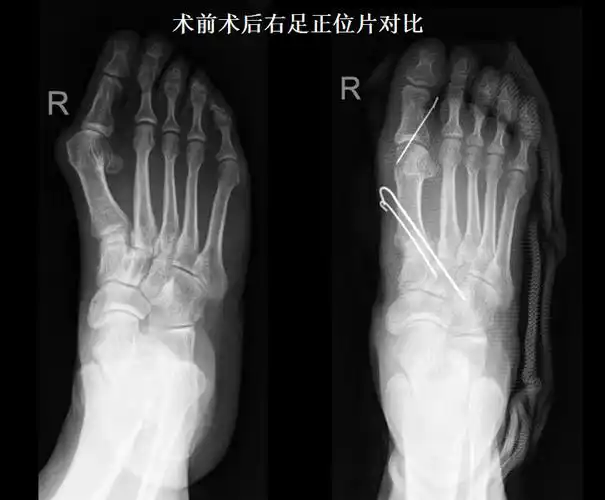

陈圣英分析拇外翻矫正削骨不是关键矫正才是关键